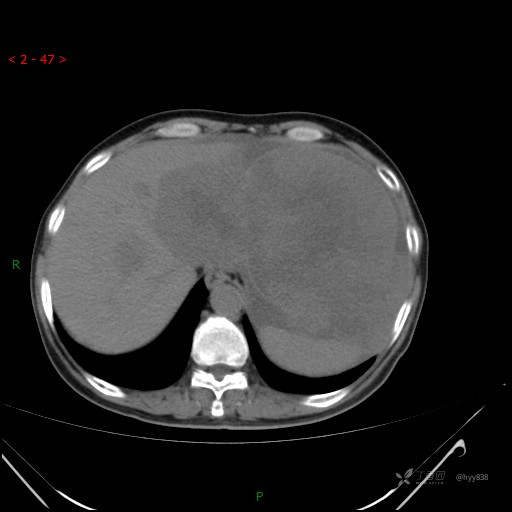

增强动脉期